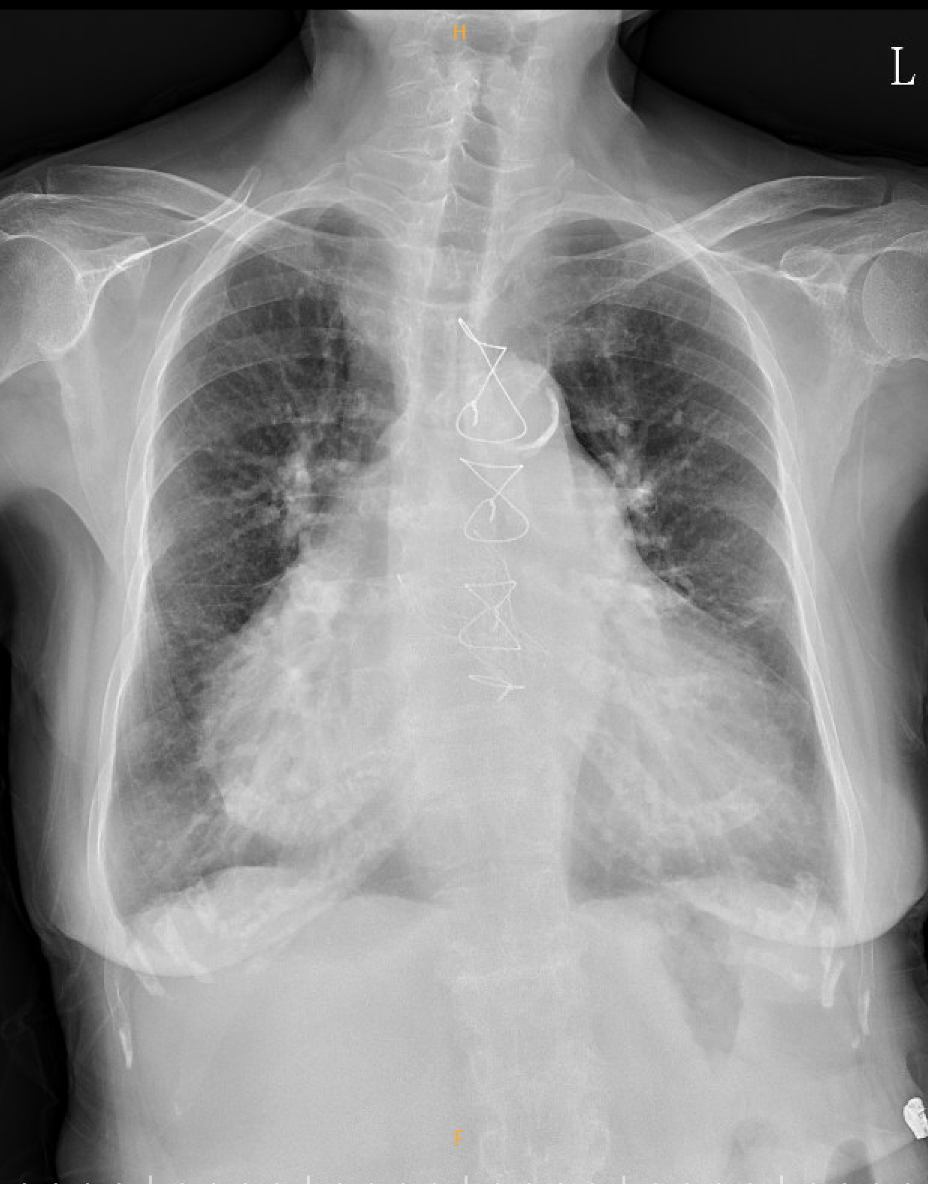

A 78-year-old woman with a long-standing history of rheumatic heart disease presented with complex multivalvular involvement, including MR, MS, AR and AS. She underwent two mitral valvuloplasties in her third and fourth decades of life and subsequently received combined surgical aortic valve replacement (AVR) and mitral valve replacement (MVR) in 2015, TAVR-in SAVR procedure in 2022 due to recurrent heart failure. However, in 2025, physical examination showed pitting edema and lung edema again.

Relevant Test Results Prior to Catheterization

Laboratory examination: Hb: 6.3 g/dL, MCV 111.7 fL, Plt 246 k/uL, Reticulocyte 6.8 %, Iron 90 ug/dL, TIBC 326 ug/dL, ferritin 375 mg/mL, LDH 1025 U/L, Haptoglobin < 27.20 mg/dL, Creatinine 1.61 mg/dL, BUN 66.6 mg/dL, Total billirubin 1.44 mg/dL, ALT 14 U/L, NT-proBNP 9340 pg/mL

Echocardiogram: TTE and TEE

- LVIDd 40 mm, LA 68 mm, LVEF 70.9%, Ao mean PG 16.1 mmHg

- Increasing trans-aortic valve mean pressure gradient